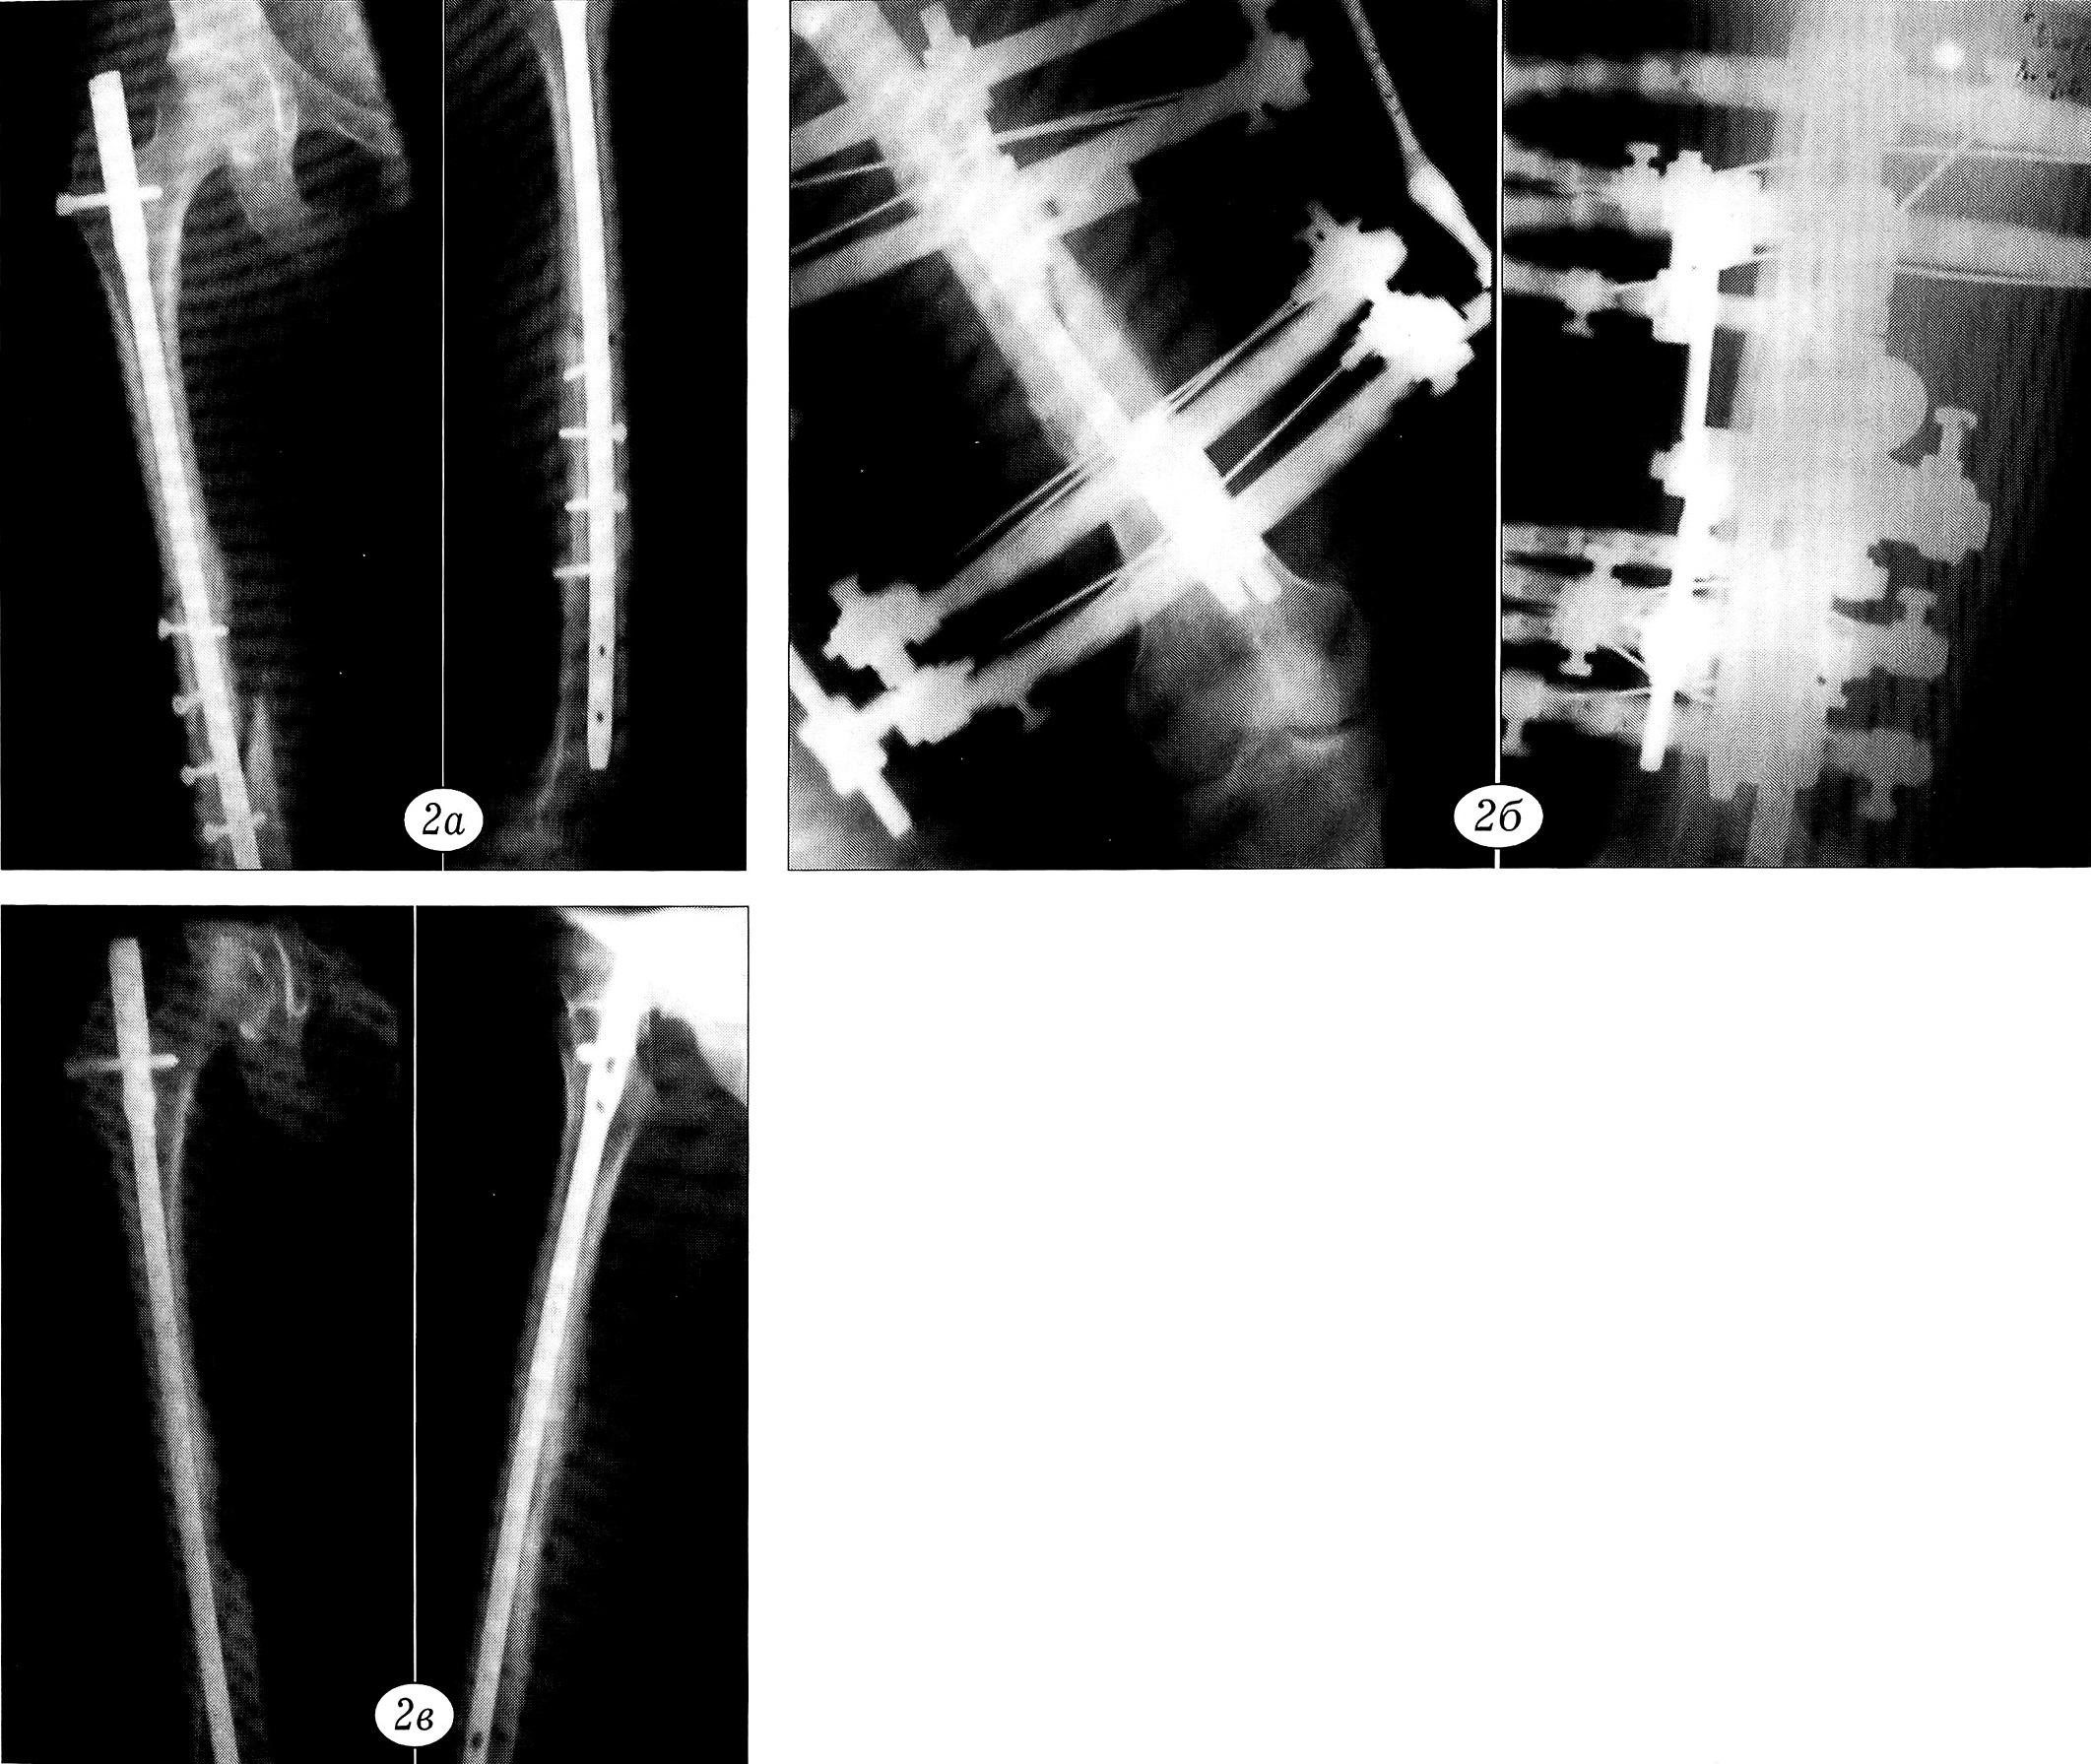

Пример 2. Больная Е., 23 лет, в автомобильной аварии получила закрытый оскольчатый перелом правого бедра в средней трети. В московской больнице вблизи места происшествия произведен остеосинтез металлическим блокируемым гвоздем с шурупами. Консолидации перелома не наступило. При обращении в ЦИТО спустя 6 мес после травмы: мышцы правого бедра резко атрофированы, на рентгенограммах — несросшийся перелом бедренной кости (рис. 2, а). Без удаления штифта наложен аппарат внешней фиксации. Через 4,5 мес клинически и рентгенологически отмечается консолидация перелома (рис. 2, б). Аппарат демонтирован. Штифт удален спустя 8 мес (рис. 2, в).

Рис. 2. Пример 2.Рентгенограммы больной Е.a — несросшийся оскольчатый перелом бедренной кости через 6 мес после остеосинтеза интрамедуллярным штифтом и винтами;б — через 4,5 мес после наложения аппарата наружной фиксации: консолидация перелома;в — после демонтажа аппарата.